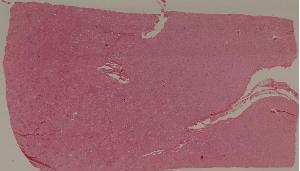

48.病毒性心肌炎

49.梅毒性主动脉炎

50.大叶性肺炎

51.肺肉质变

52.小叶性肺炎

57.肺癌

59.慢性萎缩性胃炎

60.胃溃疡

61.胃腺癌(胃粘液腺癌)

62.急性普通型病毒性肝炎

63.慢性活动性肝炎

64.急性重型病毒性肝炎

65.亚急性重型病毒性肝炎

66.活动性结节性肝硬化

67.非活动性结节性肝硬化

68.胆汁性肝硬化

69.肝细胞性肝癌

72.膜性肾小球肾炎

73.急性肾小球肾炎

74.新月体性肾炎